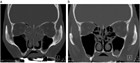

1. 嗅覚障害は発生部位から、気導性嗅覚障害、嗅神経性嗅覚障害、中枢性嗅覚障害に分類される。

1. 半数近くが鼻副鼻腔炎による気導性嗅覚障害である。